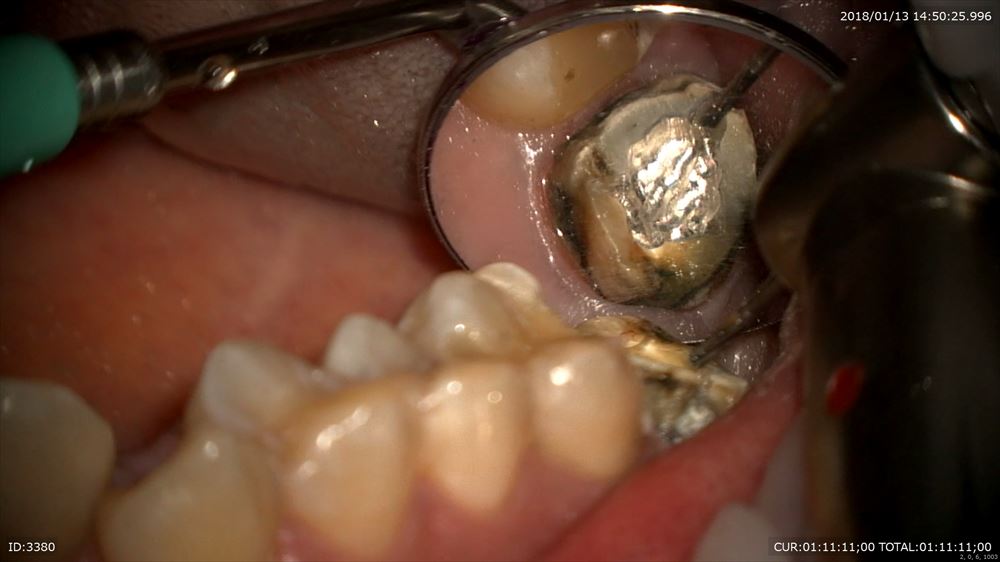

最後のケースは虫歯治療、奥歯編。マイクロスコープを使用すると通常の機種はミラーテクニック(鏡越しに治療)で行う事が多いです。しかし当院で使用しているカールツアィスピコモラーはモラーシステムがついていますので奥歯も直視で行える事が多いです。

これも銀歯虫歯。銀歯の下は必ず虫歯になります。

中は 感染だらけ。下の7番の近心。直視で虫歯除去、マージンを研磨

MTAセメントで術後の疼痛緩和対策。